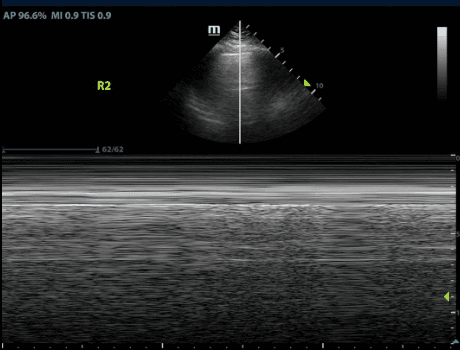

M-mode, or Motion mode, is a type of ultrasound modality that displays motion of a structure through time. See our post on Lung Sliding for more information on using M-mode to diagnose a pneumothorax.

Being highly specific for pneumothorax, the lung point delineates the border of the collapsed lung and allows for determining the actual size of the condition. Remarkably specific for pneumothorax, it precisely outlines the border of the collapsed lung. Clinically, the distance is often assessed laterally between the sternum and the lung point, with larger pneumothoraces exhibiting a more lateral and posterior lung point.